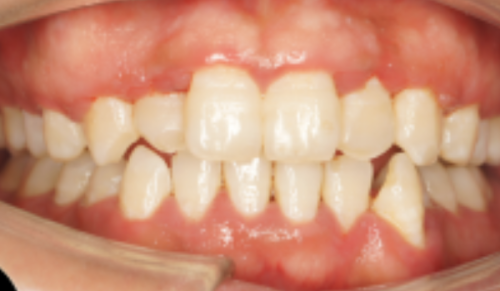

(二)成都布莱梅联合口腔医院牙齿矫正技术介绍

成都布莱梅联合口腔医院是采用隐适美iTero口扫仪快速生成3D牙模并模拟矫正过程。主打德国数字化根控技术和数字化根控导板正畸,通过多学科联合会诊,提高了矫正的安心性和速度,误差控制在0.005mm以内。

成都布莱梅联合口腔医院医生会根据患者的具体情况制定个性化的矫正方案,结合面部美学设计,不仅能矫正牙齿,还能提升面部整体美观度,因此在患者中口碑良好。